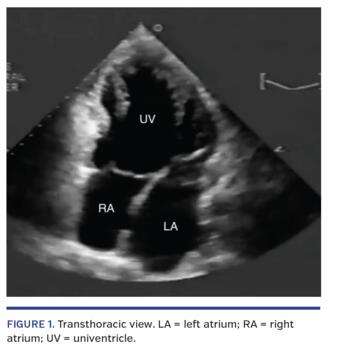

An 18-year-old male patient with an unknown past medical history presented to the emergency room with complaints of palpitations and paroxysmal episodes of shortness of breath over a 7-year period. The patient was from Uruguay and visiting the United States when symptoms occurred. He had been told in the past that he had a heart defect, but was never treated surgically or medically. On physical examination, the patient was slightly tachycardic with a systolic murmur noted adjacent on the left fourth intercostal space. Crackles were noted in the lower lung fields bilaterally. The patient looked adequately nourished with average build, along with grade 1 clubbing of his digits. Blood pressure was 100/64 mm Hg with a heart rate around 120 beats/min, saturating around 95% on room air. His dyspnea improved with supplemental oxygen over several minutes. Electrocardiogram demonstrated atrial flutter. Chest x-ray showed moderate pleural effusions bilaterally with a smaller-than-expected heart. Transthoracic echocardiography displayed a univentricle with an ejection fraction of approximately 45% (Figure 1 and Video 1). No other cardiac pathologies were noted. Cardiac catheterization and surgical interventional options were presented to the patient, but he refused and was lost to follow-up.